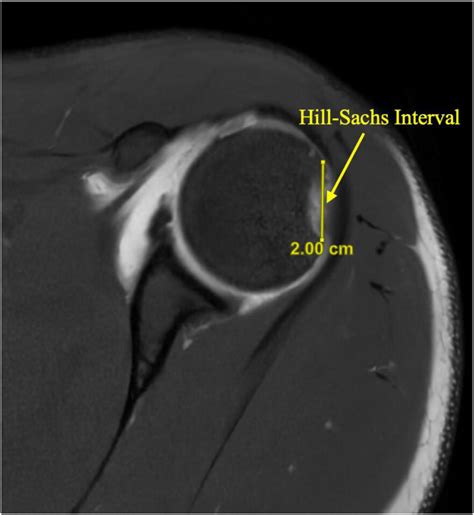

• Imaging studies: Imaging studies, such as X-rays, CT scans, or MRI scans, can help visualize the Hill Sachs lesion and assess its size and location. MRI scans are particularly useful for evaluating the soft tissues around the shoulder joint.

Hill Sachs disease is named after the doctors who first described it, Dr. Harold Arthur Hill and Dr. Maurice Sachs. It is a common complication of shoulder dislocations, particularly anterior dislocations. The condition involves a defect or indentation on the posterolateral aspect of the humeral head, which can range from a small depression to a large, irregular deformity.

When the shoulder dislocates anteriorly, the humeral head is forced out of the glenoid fossa and impacts the anterior glenoid rim. This impact can cause a compression fracture of the humeral head, leading to the characteristic Hill Sachs lesion. The size and location of the lesion can vary, depending on the severity of the dislocation and the individual's anatomy.